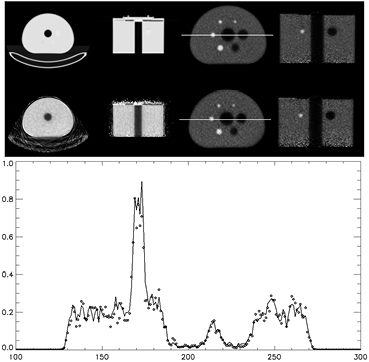

Standard image High-resolution image3.5. Reconstruction of emission data with Lu-176 transmission data and MLACF

The attenuation map created using the Lu-176 decays have some inaccuracies but are still useful for larger objects. These attenuation maps generally define the boundaries of the object being scanned fairly well. Using the Lu-176 attenuation maps, the scatter correction can be performed on the object and the resulting scatter correction sinogram is inputted to the MLACF algorithm. The Lu-176 attenuation map can also be used as a starting image for the attenuation estimate of MLACF. The image quality phantom's data from the previous section was reconstructed using the MLACF algorithm with 5 iterations and 24. The resulting emission and attenuation maps are shown in figure 11.

Figure 11. Attenuation maps derived for CT (top right) and estimated with MLACF (bottom right). Right images are the corresponding PET emission reconstructions. Lower plot is of the profile across the images shown by the white line in the above images using attenuation maps from CT (-) and Lu-176 with the MLACF algorithm (◊).

Download figure:

Standard image High-resolution imageThe attenuation map shown in figure 11 is an estimate from MLACF and shows that the internal structures are well defined with respect to the attenuation map derived from just Lu-176 data (figure 10). There is some disadvantage to the MLACF attenuation map in that there is no estimation for the line of responses that have no emission data. The bed and the shell of the phantom are not recovered but do not seem to vary much from the starting image. The center hole is recovered and the emission reconstruction now has no emission contamination in the center cold region of the phantom as seen in figure 10. Although the images are similar, the comparison is challenging as the two emission images are reconstructed using different algorithms with different objective functions and convergence rates. An observation is that the uniform regions do appear uniform with no visible artifacts. The sphere recovery is similar between the two cases and the iterations were selected to try to achieve similar noise structure between the two cases.

4. Discussion